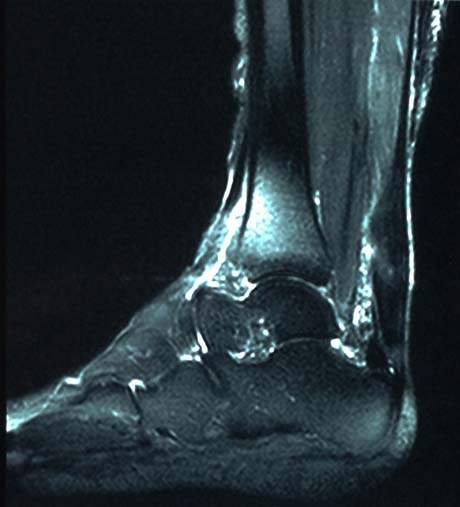

Partial rupture of the Achilles tendon